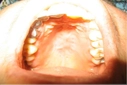

4. İnflamatuar HastalıklarBazı inflamatuar hastalıklar, dil ve damak uyuşmasına neden olabilir. Örneğin, ağızda meydana gelen aftlar veya lökoplaki gibi durumlar, dilin hissini etkileyebilir. Ayrıca, romatoid artrit gibi sistemik inflamatuar hastalıklar da sinirlerin etkilenmesine yol açabilir.